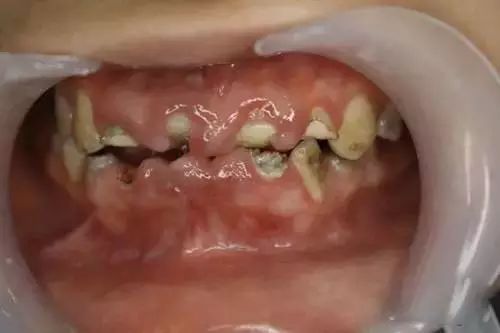

在最极端的状态下,它甚至可以毁掉你的整口牙齿!

如下图

这是一个来自美国的真实案例。这位酷爱可乐的男孩年纪轻轻就失去了所有的牙齿不得不装上全口假牙。

在医学领域,这一现象被称作“酸蚀症”,简单来说就是牙齿长期广泛接触酸性物质造成的牙齿硬组织溶解丧失。